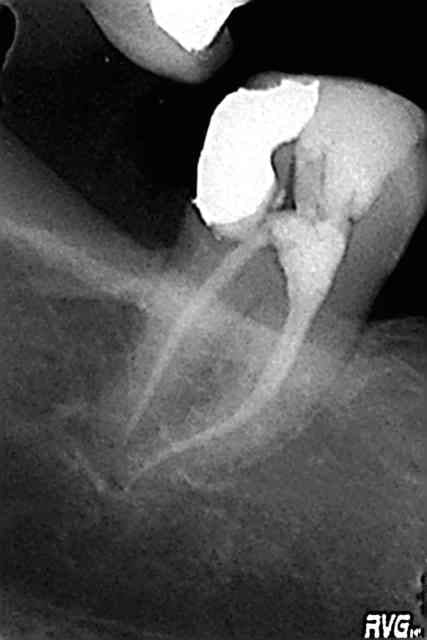

Tiens puisque c'est la journée des courbures, l'endo de ce soir. Protaper tout con aussi (digue, cathétérisme, S1, S2, F1, F2, gutta condensor) sur 48 (47?) 2 canaux, CMU.

edit : il est prévu de couronner cette dent, dans le cadre d'un relèvement général de la DV, sur la radio c'est un simple pansement + l'ancien amalgame distal. merci de votre lecture !